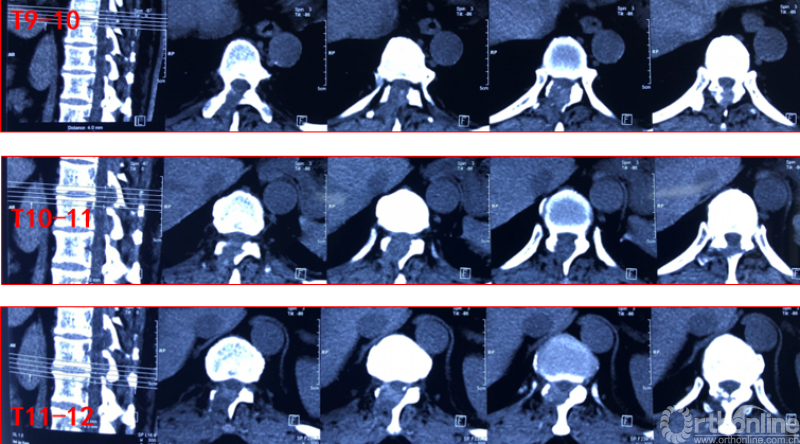

术前资料

术中资料

术后影像学资料

术后第二天资料

术后病情评估

术后第二天

JOA评分:8分;RR:37.5%(可);ASIA等级:D级。

术后8个月资料